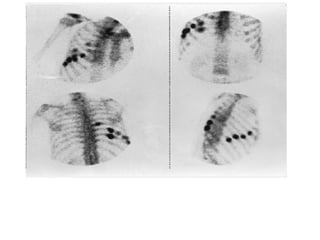

Multiple Rib Fractures. Vigorous osteoblastic

repair activity is seen in two rows of fractures, which were not

visible on radiographs.